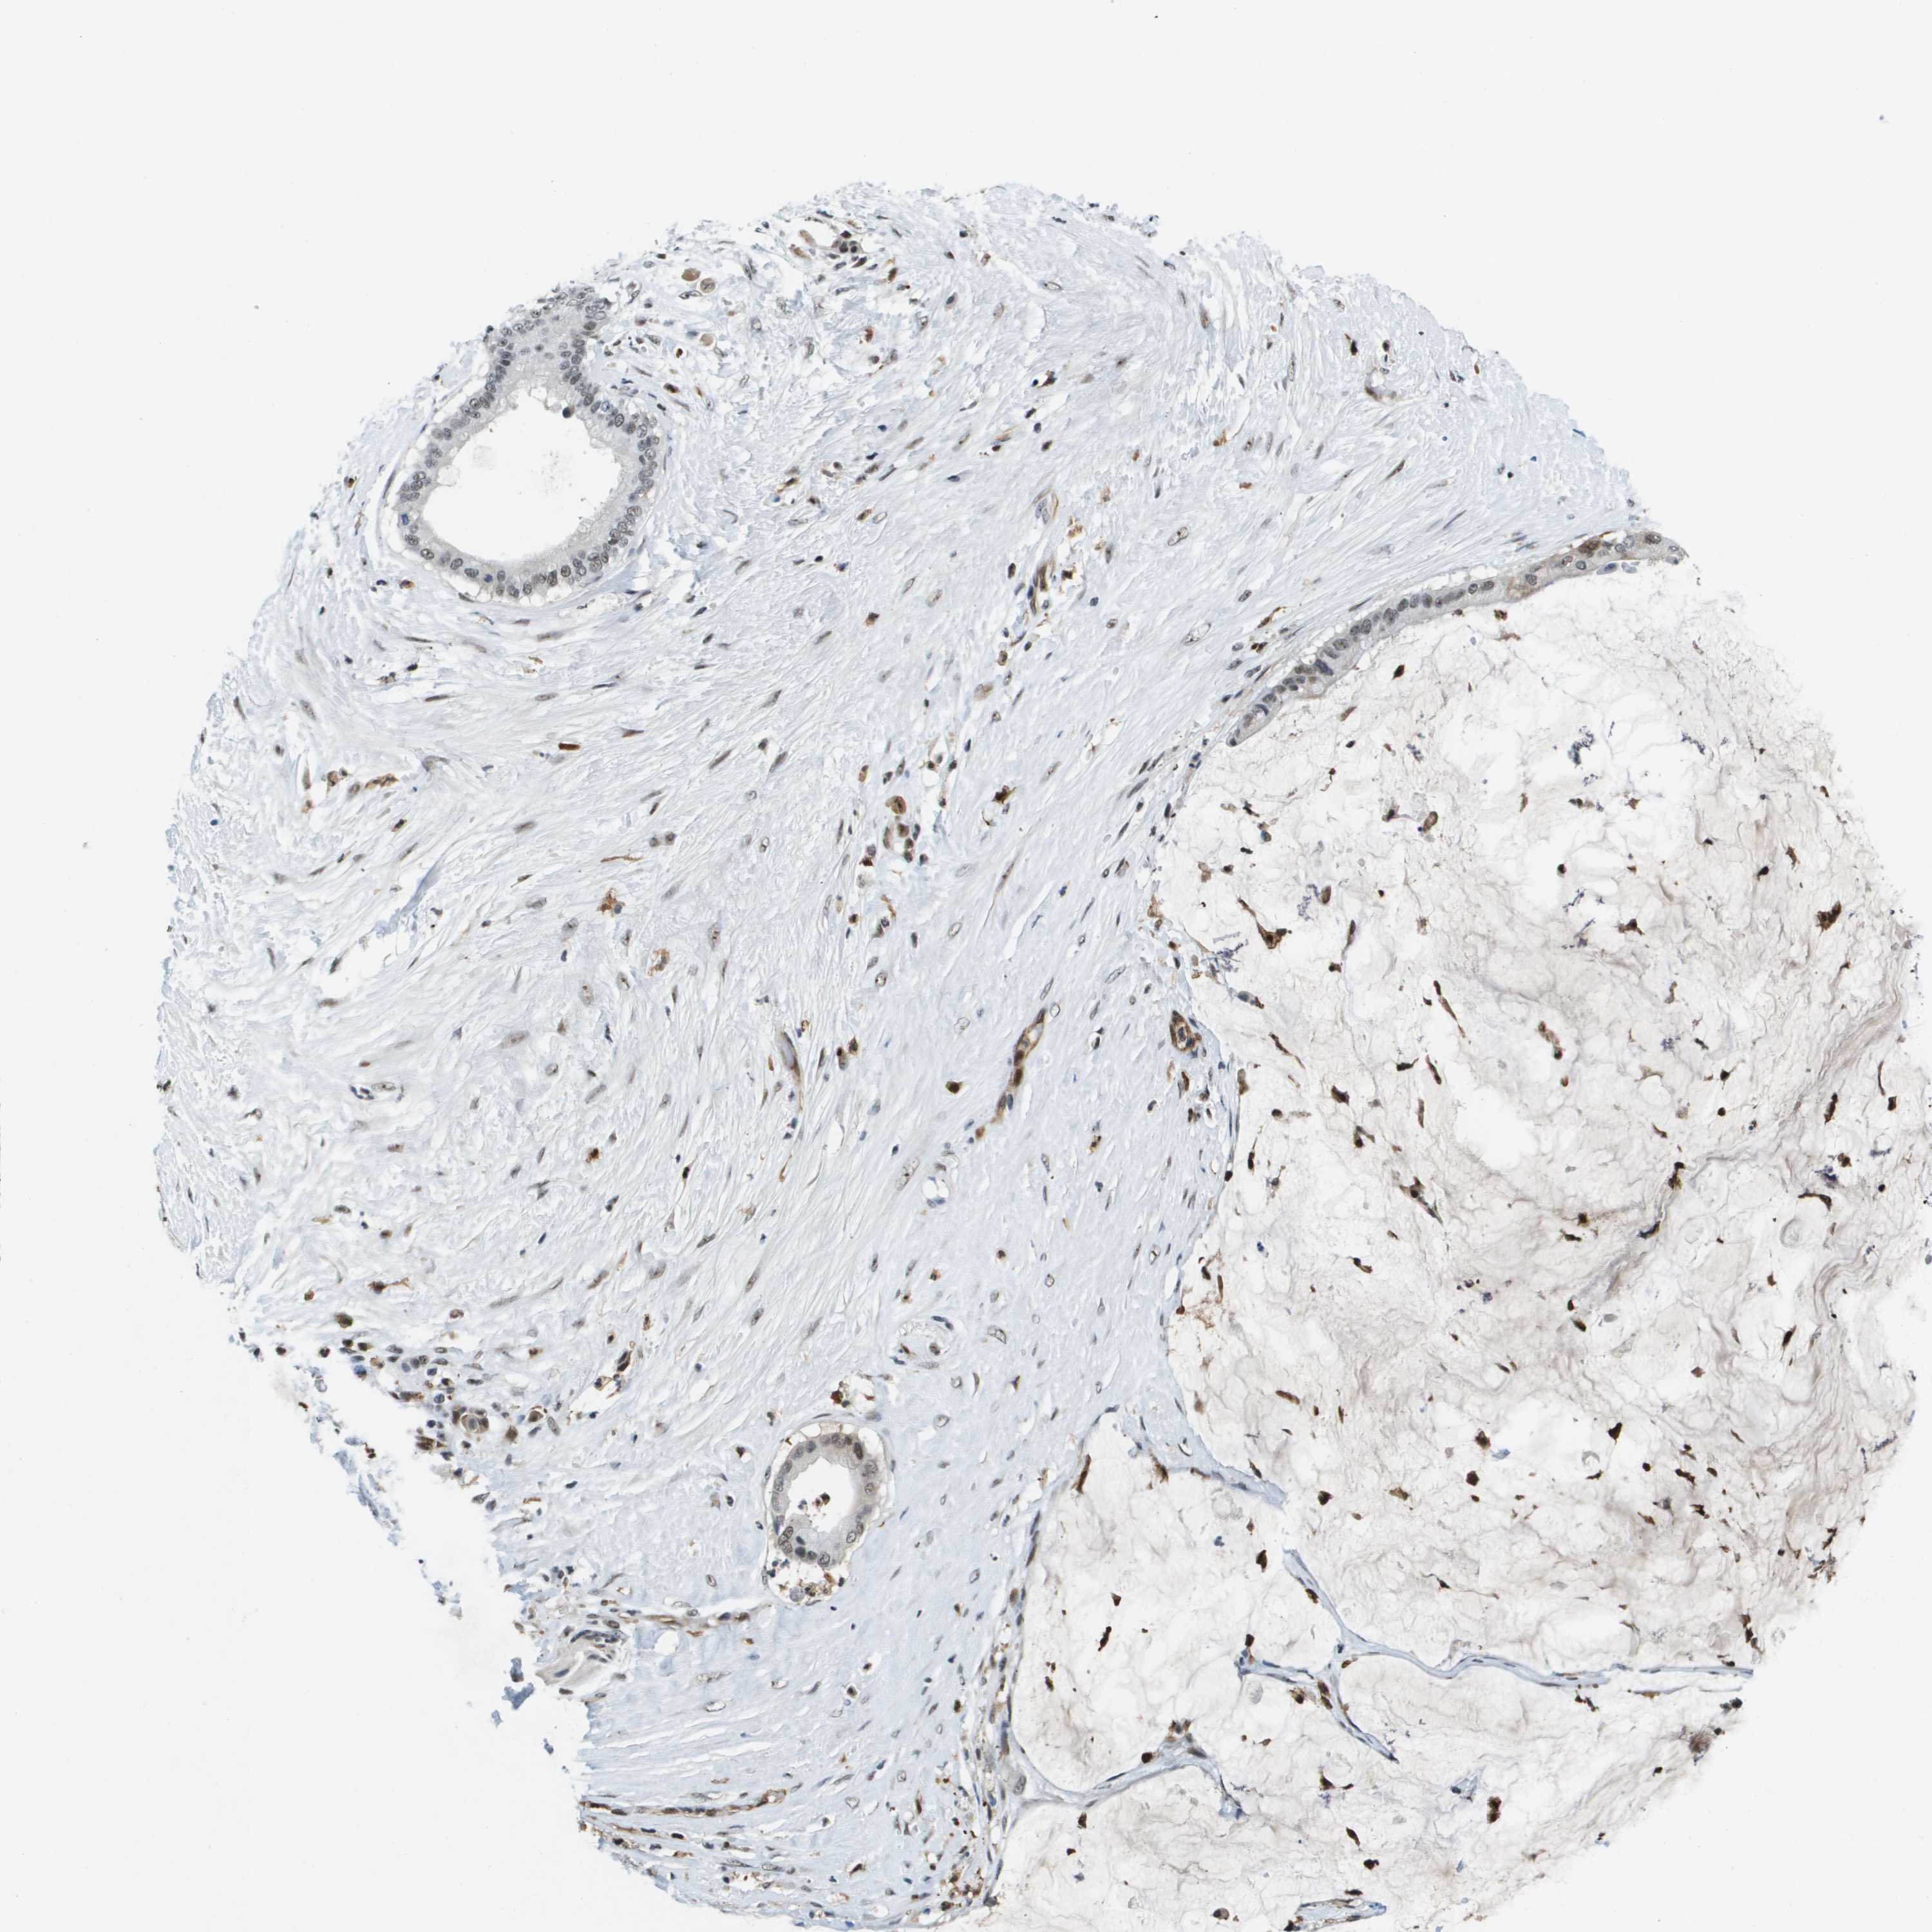

PANCREATIC CANCER - Protein expressioni

A mouse-over function shows sample information and annotation data. Click on an image to view it in a full screen mode. Samples can be filtered based on level of antibody staining by selecting one or several of the following categories: high, medium, low and not detected. The assay and annotation is described here.

Note that samples used for immunohistochemistry by the Human Protein Atlas do not correspond to samples in the TCGA dataset.

Antibody stainingi

Antibody staining in the annotated cell types in the current human tissue is reported as not detected, low, medium, or high, based on conventional immunohistochemistry profiling in selected tissues. This score is based on the combination of the staining intensity and fraction of stained cells.

Each image is clickable and will lead to virtual microscopy that enables deeper exploration of all samples and also displays staining intensity scores, fraction scores and subcellular localization as well as patient and tissue information for each sample.

Antibody HPA016704

Staining

High

Medium

Low

Not detected

Intensity

Strong

Moderate

Weak

Negative

Quantity

>75%

75%-25%

<25%

None

Location

Nuclear

Cytoplasmic/membranous

Cytoplasmic/membranous,nuclear

Adenocarcinoma, NOS